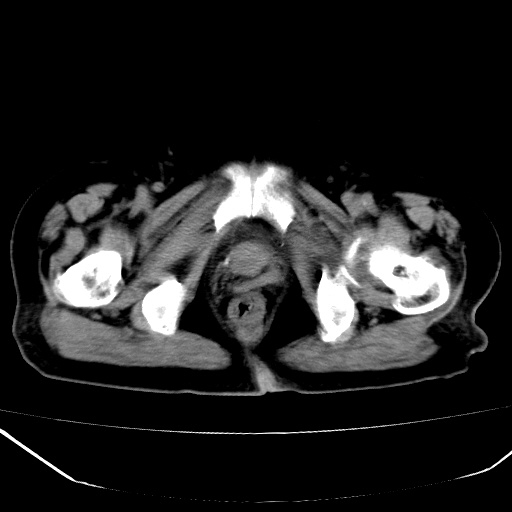

患者,女,74岁,无不适,b超示盆腔包块。

子宫前上方巨大脂性肿物,肿物边缘为较厚软组织密度影,其内缘欠光整,脂性密度中央见结节状软组织密度影“漂浮”,肿物与子宫前壁关系密切,考虑1脂肪瘤2皮样囊肿3肌瘤脂样变

ct值-90hu